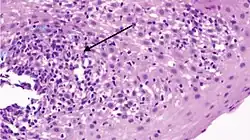

| Pathology image of lymphocytic esophagitis (H&E stain). The image demonstrates common findings in the condition: dense peripapillary lymphocytic infiltrate with spongiosis (arrow), and absence of neutrophils and eosinophils. | |

While the histologic changes in the biopsies are characterized by the presence of an inflammatory infiltrate, consisting primarily of lymphocytes in the absence of other inflammatory cells such as granulocytes, the criteria for making the diagnosis are still unclear.[1][4] The location of the biopsies, cutoff of number of lymphocytes found in each high-power field of view of the microscope, the presence of spongiosis, and the need for immunohistochemical staining to define lymphocytes are all unclear still.[1]